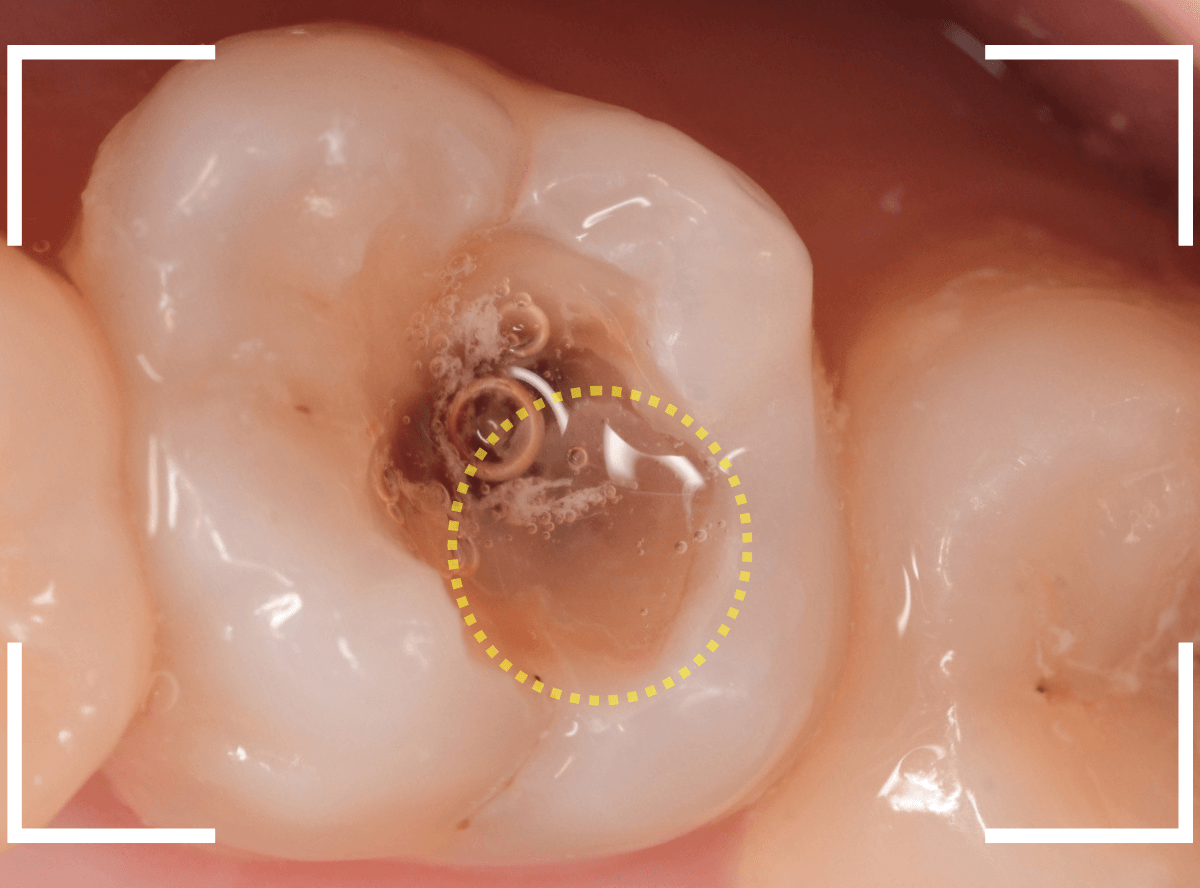

Case.14 CR(コンポジット・レジン)の下の深い虫歯

奥歯で咬んだ時に、痛みを感じるという訴えで来院された患者さんです。

パッと見は特に問題なさそうな状態ですが、大きなレジン治療がしてあり、レジンの奥もボヤっと黒っぽく見えてアヤシイ感じです。

麻酔をして、治療を開始します。

レジンを外すと、中から出血してきました。

これは、歯のスキマに歯肉が入り込んでしまったために起こってしまったものです。

おそらく、随分前から虫歯が進行していたと思われます。

止血しながら、電気メスで歯の中に入り込んだ歯肉を除去します。

虫歯と入り込んだ歯肉でぐちゃぐちゃになっている状態でした。

慎重に全ての虫歯を除去したところです。

〇部が神経の入り口が見えているところです。

神経を保護する処置をして、しばらく経過観察しますが、痛みが出て神経を除去する必要が出る可能性も高いです。

痛みが出ませんように・・・。